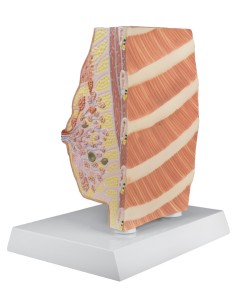

Modello per palpazione del seno, tre seni singoli su supporto - 3B Scientific L55

Modello per palpazione del seno, tre seni singoli su supporto - 3B Scientific L55

Dal cranio in 22 parti con incastri magnetici ai modelli di colonna vertebrale, da quelli di articolazioni a quelli di cuore, ogni pezzo della nostra collezione è progettato per un’immersione totale nello studio dell’anatomia umana. I nostri modelli, realizzati tramite scansioni di ossa vere, garantiscono un’esperienza tattile autentica e una fedeltà di peso quasi identica agli originali.

Essenziali per studenti e professionisti, i nostri modelli anatomici sono strumenti didattici che permettono di osservare le strutture anatomiche con precisione, eliminando la necessità di dissezioni o studi invasivi. Sono inoltre utili per spiegare ai pazienti le patologie, rendendo la comunicazione più efficace e risparmiando tempo prezioso.